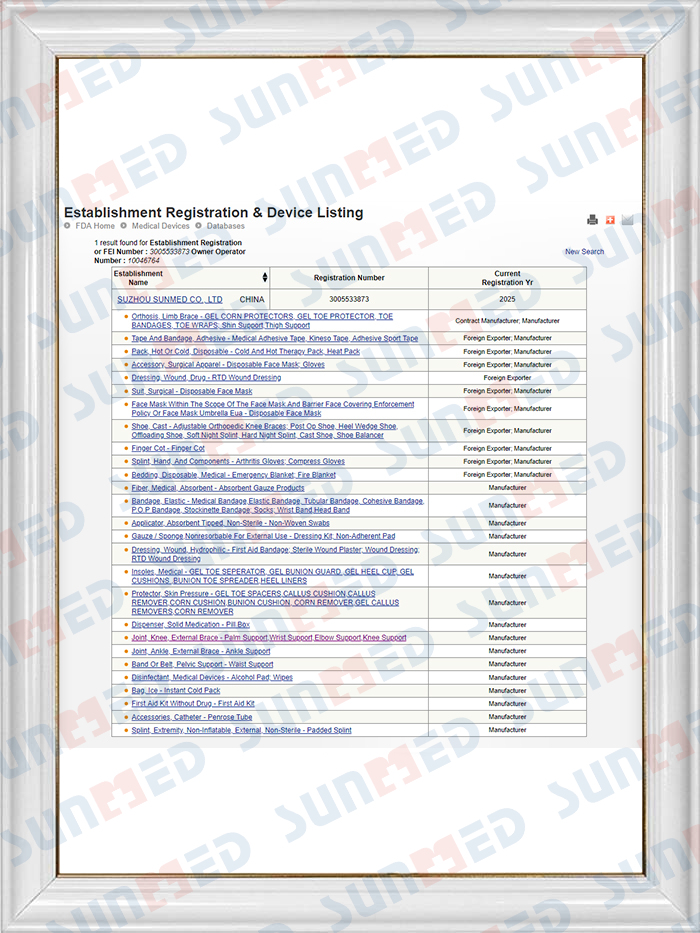

- Про нас